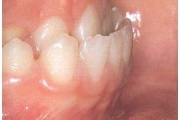

Ravijärgne seis. Jäävhammas on täielikult lõikunud.

) Röntgenülesvõte. Ülemise esimese jäävmolaari lõikumine on takistatud 2. piimamolaari tõttu

Esimese jäävmolaari ektoopiline lõikumine